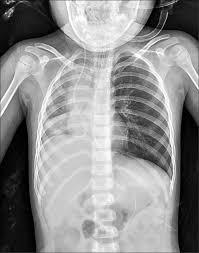

抵達醫院時,男童血氧一度維持在97%,但呼吸狀況明顯異常。醫療團隊立刻安排X光攝影與耳鼻喉科會診,然而兩次鼻咽鏡檢查都沒發現任何異物,影像報告看起來一切正常。但詭異的是,孩子的血氧數值忽高忽低,最低時僅剩下63%,只能仰賴高濃度氧氣勉強維持生命跡象,情況相當危急。

圖片來源:《自由時報》,示意圖。

深夜轉入加護病房後,醫師決定使用軟式支氣管鏡深入檢查,真相這才揭曉——原來有一顆花生卡在氣管裡,隨著呼吸節奏上下劇烈晃動,阻塞超過七成的氣道,形成致命的「球閥效應」,空氣能進卻無法順利排出,臨床上稱為「跳舞花生」。即便完成插管,花生仍持續移動,男童呼吸速率飆到每分鐘49次,低血氧問題始終無法改善。隔天清晨,花生滑進右主支氣管,導致右肺完全塌陷、縱膈腔偏移,情況更加惡化。醫療團隊緊急推進手術室,改用專門移除異物的硬式支氣管鏡處理,耳鼻喉科醫師順利取出這顆折磨孩子將近24小時的花生,術後血氧終於穩定回升至99%。